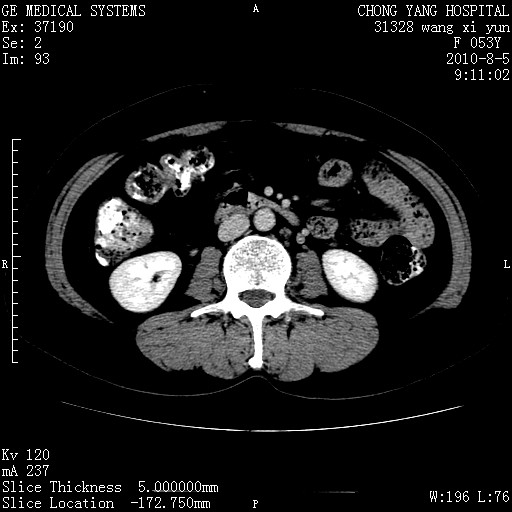

标题: CT28214:F41Y 血尿二十天,建议盆腔平扫加增强。

1)考虑肝左叶胆管细胞癌。2)脂肪肝。